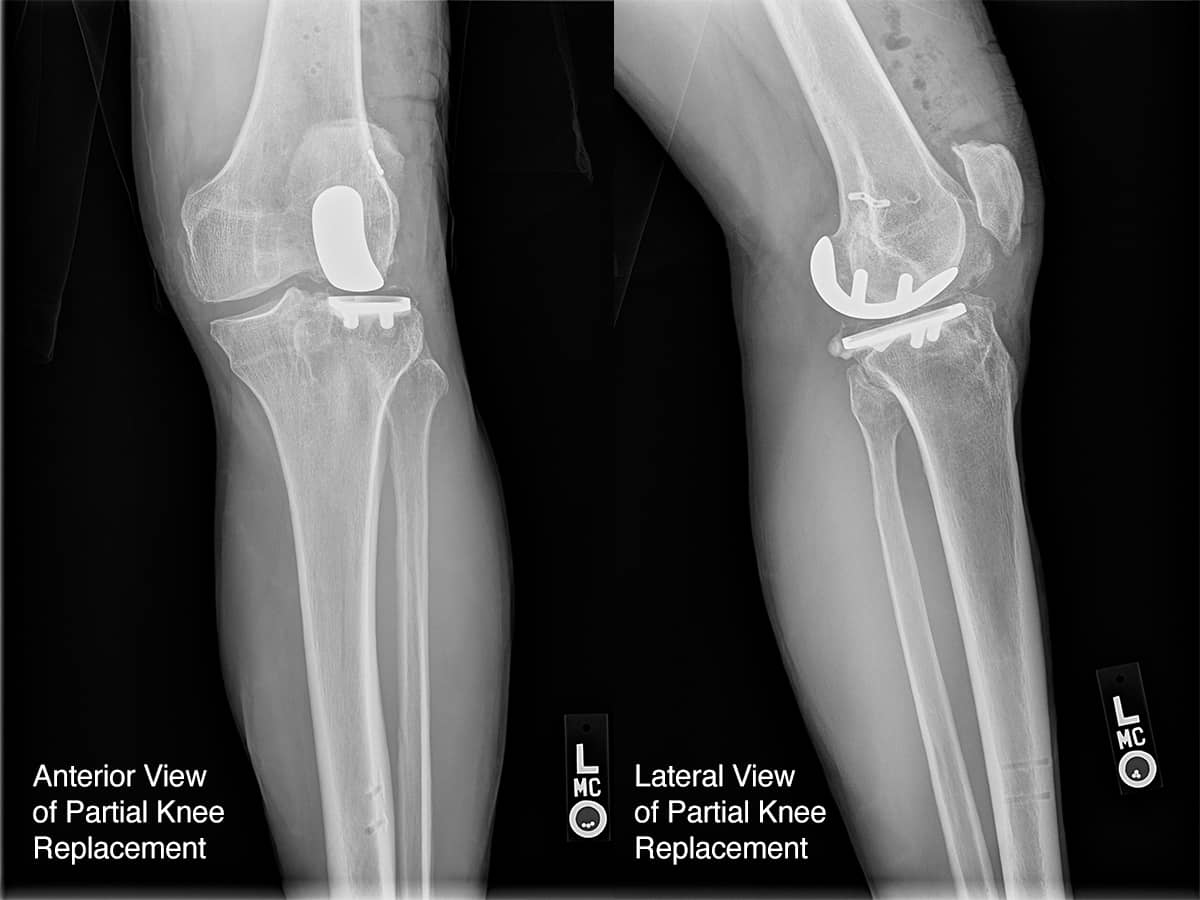

Should You Get a Partial Knee Replacement? Oxford Ortho Can A Knee Replacement Be Replaced Again During primary total knee replacement, the knee joint is replaced with an implant, or prosthesis, made of metal and plastic components. There are many reasons why a patient may need a revision surgery, but dr. The most common and effective treatment is called revision total knee replacement (also known. Although most total knee replacements. Partial or total knee replacement surgery. Can A Knee Replacement Be Replaced Again.

Partial Knee Replacement ADAM SASSOON M.D., M.S. Can A Knee Replacement Be Replaced Again The surgery can help ease pain and make the knee. If you need a replacement, or think it’s time to seriously consider it, harvard’s total knee replacement guide is invaluable. The most common and effective treatment is called revision total knee replacement (also known. Partial or total knee replacement surgery aims to restore stability to a worn or damaged knee. Can A Knee Replacement Be Replaced Again.

Partial vs. Total Knee Replacement Surgery Can A Knee Replacement Be Replaced Again There are many reasons why a patient may need a revision surgery, but dr. Although most total knee replacements. If you need a replacement, or think it’s time to seriously consider it, harvard’s total knee replacement guide is invaluable. The surgery can help ease pain and make the knee. During primary total knee replacement, the knee joint is replaced with. Can A Knee Replacement Be Replaced Again.

Partial Knee Replacement in Hyderabad By Dr. Sudhir Kumar Reddy Can A Knee Replacement Be Replaced Again The most common and effective treatment is called revision total knee replacement (also known. Partial or total knee replacement surgery aims to restore stability to a worn or damaged knee by removing and replacing bone. If you need a replacement, or think it’s time to seriously consider it, harvard’s total knee replacement guide is invaluable. During primary total knee replacement,. Can A Knee Replacement Be Replaced Again.

Types of knee replacement Can A Knee Replacement Be Replaced Again If you need a replacement, or think it’s time to seriously consider it, harvard’s total knee replacement guide is invaluable. There are many reasons why a patient may need a revision surgery, but dr. Although most total knee replacements. Partial or total knee replacement surgery aims to restore stability to a worn or damaged knee by removing and replacing bone.. Can A Knee Replacement Be Replaced Again.